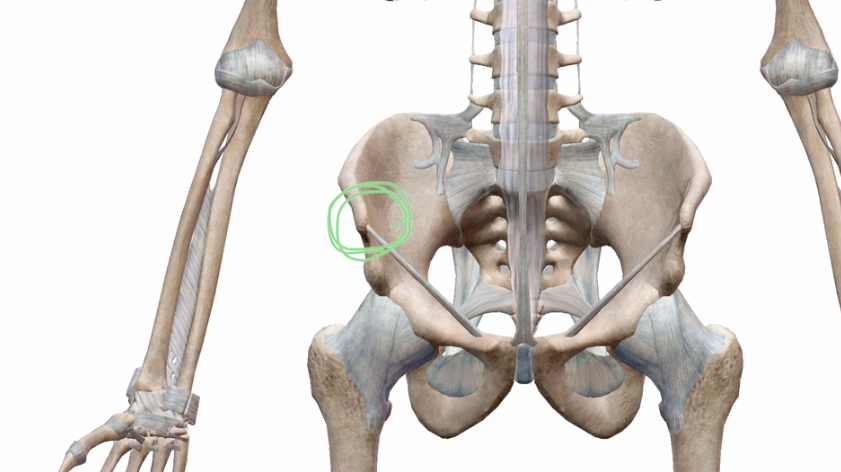

とにかく、ココです↓

体を透かして見るとこんな感じです↓

この骨が出っ張っているところが上後腸骨棘です。

お尻あたりを触るとお尻の割れ目の少し上外側あたりにある出っ張ったところです。